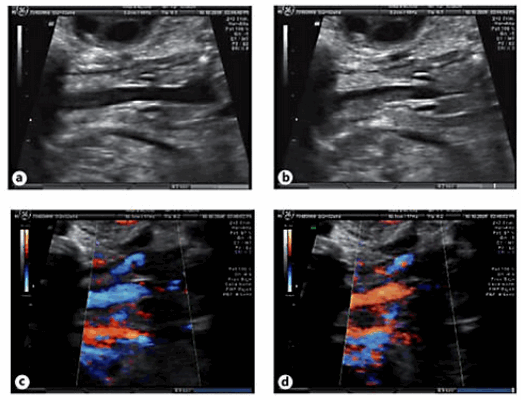

Следующим этапом была оценка голосовых связок на УЗИ. Для этого было проведено сканирование в корональной плоскости на уровне шеи плода, что позволило визуализировать трахею, гортань и голосовые связки. Мы систематически оценивали анатомические данные и функциональные возможности, включая нормальный вид; оценивали движения открытия-закрытия голосовых связок в трахею; прохождение жидкости через трахею с помощью цветной допплерографии (рис. 1).

Рис.1. Корональный срез шеи плода на уровне трахеи, который показывает нормальный внешний вид гортани и голосовых связок с нормальным открытием (а) и закрытием (б) просвет трахеи при прохождении жидкости. Изображения (с) (d) движения жидкости по трахеи с использованием цветного допплера.